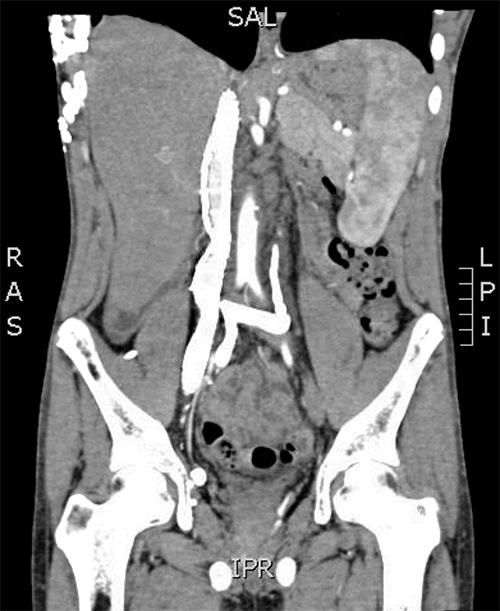

Prior to his transplant, the patient underwent recanalization of the right EIV, right CIV, and the IVC up to the hepatic veins with multiple self-expanding stents (Figure 1). The IVC recanalization was achieved by establishing the right common femoral vein access under ultrasound guidance and negotiating a catheter-supported straight-tipped hydrophilic wire across the length of the iliac vein and the occluded IVC under fluoroscopic guidance. The successful crossing of the occlusion was confirmed with contrast injection into the right atrium. The length of the occlusion was initially balloon dilated and then supported with large caliber self-expanding stents, two for the IVC and one for the CIV and EIV. Postprocedure fluoroscopy demonstrated a good flow of contrast through the IVC and into the right atrium. Venous pressures were not measured in this procedure.

Figure 1. CT Abdomen Angiogram with Author Rendering. Published with Permission

A) Scan shows the self-expanding stent in the right EIV, CIV, and the entire length of IVC.

B) Left CIV is occluded and drains through the right IIV to the EIV and eventually through the recanalized IVC (author illustration).